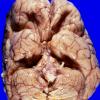

NEOPLASMS (EMBRYONAL)

Medulloblastoma, Histologically Defined

Classic Subtype (5)